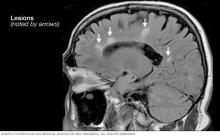

Multiple sclerosis lesions on the brain

Brain MRI scan showing white lesions associated with multiple sclerosis.

There are no specific tests for MS. The diagnosis is given by a combination of medical history, physical exam, MRIs and spinal tap results. A diagnosis of multiple sclerosis also involves ruling out other conditions that might produce similar symptoms. This is known as a differential diagnosis.

• MRI, which can reveal areas of MS on the brain and spinal cord. These areas are called lesions. A contrast dye may be given through an IV to highlight lesions that show the disease is in an active phase.